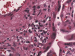

Abbildung 5a-b: Schädelsonographie Schädelsonographiebefunde. (a) Sagittalschnitt mit kolpozephalem Seitenventrikel (Stern) und Verkalkungen in den Stammganglien (Pfeil). (b) Okzipitaler Koronarschnitt mit periventrikulären und Stammganglien-Verkalkungen (Pfeile) sowie der großen Cisterna magna und der Vermishypoplasie (Stern). |

Schädelsonographiebefunde. (a) Sagittalschnitt mit kolpozephalem Seitenventrikel (Stern) und Verkalkungen in den Stammganglien (Pfeil). (b) Okzipitaler Koronarschnitt mit periventrikulären und Stammganglien-Verkalkungen (Pfeile) sowie der großen Cisterna magna und der Vermishypoplasie (Stern). |